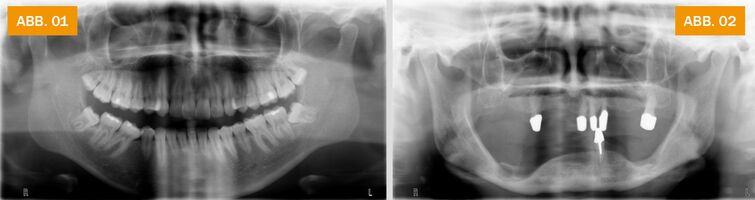

ABB.02: Röntgenbild eines älteren Menschen mit wenigen verbliebenen Zähnen. In zahnlosen Bereichen haben sich der Ober- und Unterkiefer deutlich zurückgebildet.